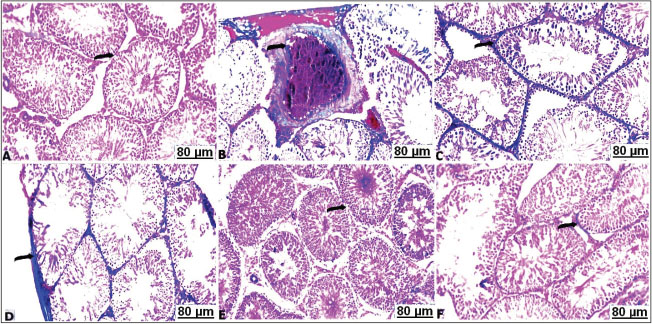

The light sections of the control testes stained with Masson's trichrome revealed thin layer of the collagen fibers (Fig. 5A). Although, CCl4 injected group manifested a significant degree of the perivascular or intertubular fibrosis was detectable by a distinct layer of the collagen infiltrated neighboring blood vessels and at the interstitium (Fig. 5B–D). Thus, CCl4 animals after treatment with a low concentration of soybean demonstrated mild distribution of collagen fibers around vasculature along the testicular tissues (Fig. 5E). As well as high concentration of dietary soybean showed minimal collagen tissues deposition (Fig. 5F).

Fig. 5. Transverse sections of testes with Masson's trichrome of the control and treated groups: A) control testes showing hard detectable collagen fibers (arrow). B,C,D) CCl4-exposed testes showing thickened interstitial tissues with collagen (arrow). E) CCl4-exposed testes+10% soybean showing unequal distribution of stained collagen fibers (arrow). F) CCl4-exposed testes+30% soybean showing apparent a decrease of the faint-stained collagen fibers (arrow).